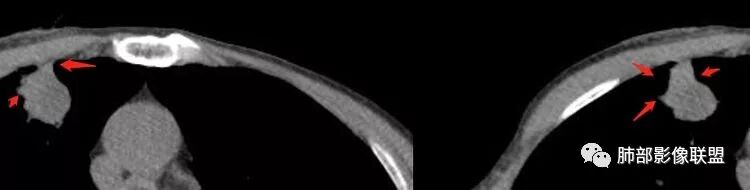

这里毛刺还是粗

转移瘤不能排除

南边:就目前的征象符合炎性,我认为炎性病变一定有但是有部分边缘膨隆,恶性不能排除,等炎性吸收后看看,或穿刺血管纠集南边:

南边:我们担心的,它是在一个转移的基础上,还有合并有炎症,担心这个隐藏在其中,因为它这个边缘,是不是很清楚光滑哈,但是我们都记得转移瘤,他很多都是边界清楚光滑的,对不对。就觉得,中间这个结节跟周围的病灶好像形态、密度各方面都不一致的。我就担心它是一个转移瘤,合并感染,周围炎性病变,中间是一个转移瘤结节这样的就麻烦了。所以常规我会建议他抗炎治疗后复查。看看那个残留的病灶怎么样,本质是如何,要么穿刺,这个病变我只能说炎性它一定有。南边:里面那个病灶就是那个类圆形的病灶,跟外面那个肯定是不一致的,就那个类圆形病灶,到底是一个转移瘤,还是单纯炎性病变的部分。目前这个片只能等复查,毕竟边缘是膨隆的,而且我们刚才也说了,转移瘤的特点,如果血道转移,他就是边界清晰光滑的。所以成这样,有这么巧的话你就没办法。南边:关于血管纠集,它就这样的,炎性病变也可以这样表现,牵拉过来,原理不同,但是影像表现已经表现很类似,我们往往关注支气管。支气管进入这个病灶的表面的时候是否堵塞,或者血管,进入这个病灶里面,是否走行是否自然;这些这些可能价值大一些,但是他是不是一个恶性征象,是;但是它的比例就是在炎性病变也不低。原发呢,不敢说没有,但是一般来说几率偏低吧。